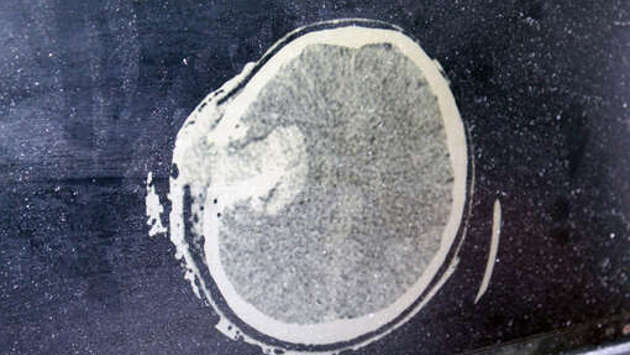

Медики спасли жизнь водителю, который получил тяжелую травму головы из-за попадания арматуры в лобовое стекло. Об этом рассказал подмосковный Минздрав. В Мытищинскую больницу самостоятельно обратился 39-летний мужчина с признаками серьезной травмы головы и кровоизлиянием в мозг. Он рассказал, что ехал на автомобиле по Ярославскому шоссе, и в какой-то момент неизвестный острый предмет пробил лобовое стекло и попал ему в голову. У мужчины диагностировали открытую проникающую черепно-мозговую травму, ушиб головного мозга тяжелой степени с внутримозговой гематомой и кровоизлиянием в вещество мозга. Требовалась срочная операция по удалению гематомы - трепанация черепа. По словам, врача-нейрохирурга Сергея Сергеева, промедление грозило бы летальным исходом, операция шла более трех часов. Пациента ввели в медикаментозную кому, в которой он находился более 10 дней. "Я плохо помню, как поступил в больницу, что произошло и какой именно предмет попал мне в голову, был в состоянии шока, держался. А потом, уже в больнице и вовсе без сознания. Но как доктор знаю, что специалисты больницы совершили большое чудо. До сих пор не верю, что я жив", - рассказал пациент. Отмечается, что пострадавший водитель - потомственный врач. Его ждет долгая реабилитация и косметическая операция по восстановлению целостности черепа, пациента уже выписали домой. Ранее нарколог рассказывал, что у пьющих водителей из-за синдрома отмены нога может соскользнуть с педали тормоза.